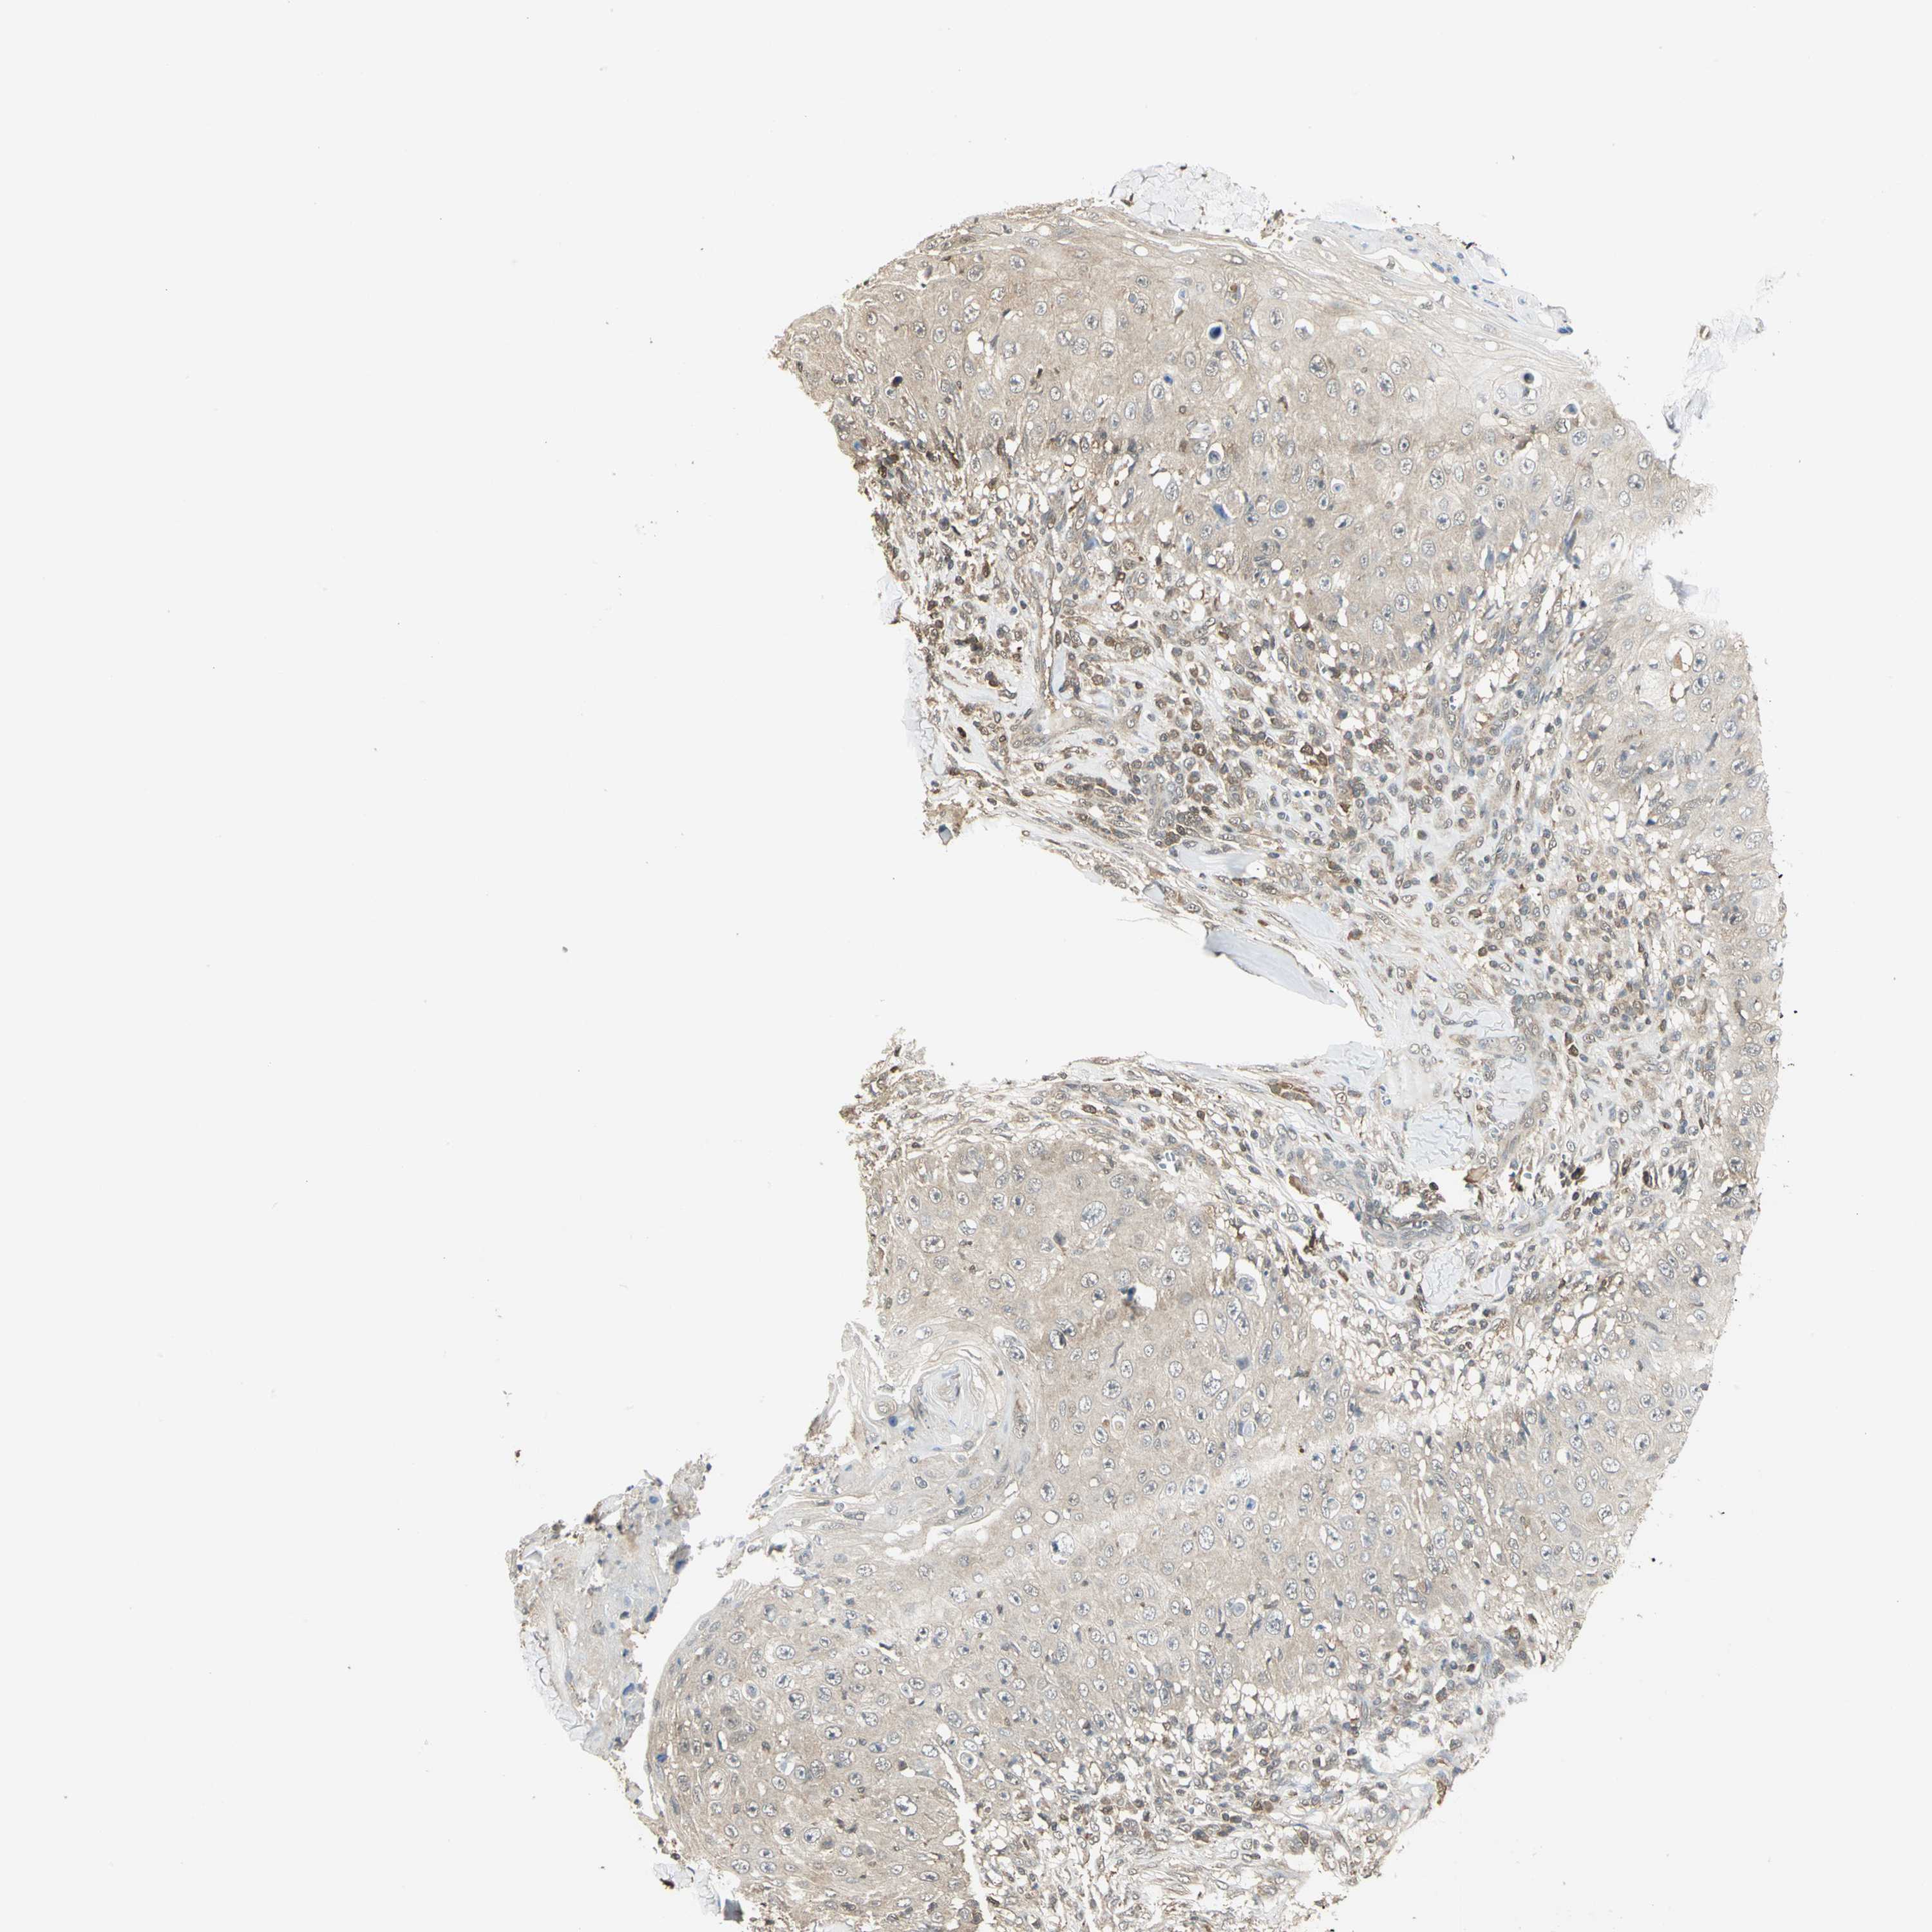

SKIN CANCER - Protein expressioni

A mouse-over function shows sample information and annotation data. Click on an image to view it in a full screen mode. Samples can be filtered based on level of antibody staining by selecting one or several of the following categories: high, medium, low and not detected. The assay and annotation is described here.

Antibody stainingi

Antibody staining in the annotated cell types in the current human tissue is reported as not detected, low, medium, or high, based on conventional immunohistochemistry profiling in selected tissues. This score is based on the combination of the staining intensity and fraction of stained cells.

Each image is clickable and will lead to virtual microscopy that enables deeper exploration of all samples and also displays staining intensity scores, fraction scores and subcellular localization as well as patient and tissue information for each sample.

Antibody HPA004190

Antibody CAB005870

Squamous cell carcinoma, NOS

Basal cell carcinoma